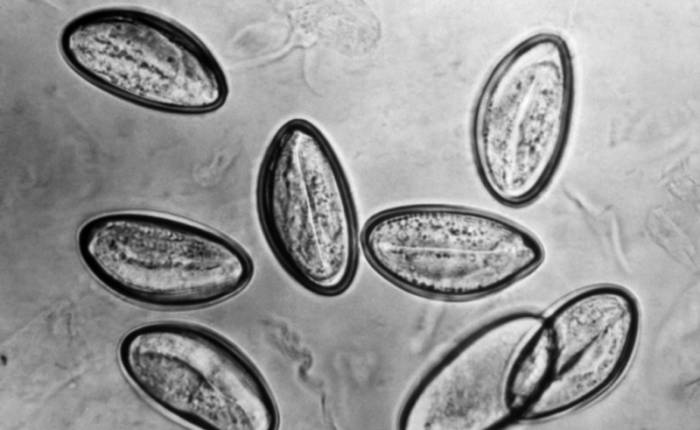

Заражение острицами происходит на фоне немытых рук. Их яйца проникают в организм и начинают свою отрицательную деятельность. У них происходит активное размножение. Если долгое время острицы остаются незамеченными они обосновываются в толстом отделе кишечника, продолжают свое плодотворное развитие и отравление организма. У одной самки глистов получается отложить 4000-10000 яиц, которые становятся новыми средствами заражения. Чтобы отложить свои яйца ей необходимо вылезть наружу из прямой кишки и оставить их там. Все эти движения чаще в основном происходят в вечернее и ночное время.

Необходимо обнаружить именно те яйца остриц, которые они отложили в районе анального отверстия. В этом и заключается суть исследования на энтеробиоз. Для правильной диагностики необходимо: